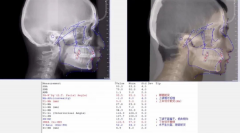

栽下梧桐树,引得凤凰来!原德阳市口腔医院正畸

2020年4月25日上午,原德阳市口腔医院正畸科主任肖世芳正式加盟暨南大学穗华...【详细】

喜讯!原德阳市口腔医院正畸科主任肖世芳正式